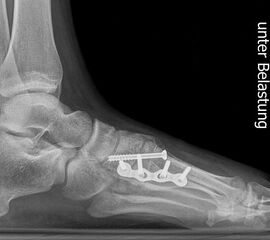

Standard ist die belastete Röntgenaufnahme des Fußes dorso-plantar und seitlich. Günstig ist eine Röhrenkippung von 10°-20°, um die Gelenke der Lisfranc-Linie einsehen zu können.

Ergänzend kann eine Schrägaufnahme hilfreich sein. Bei Metatarsalgien oder Pathologien der Sesambeine liefert die Sprinteraufnahme zusätzliche Informationen. Bei einer Pes planovalgus Fehlstellung wird ergänzend ein Saltzman view durchgeführt.